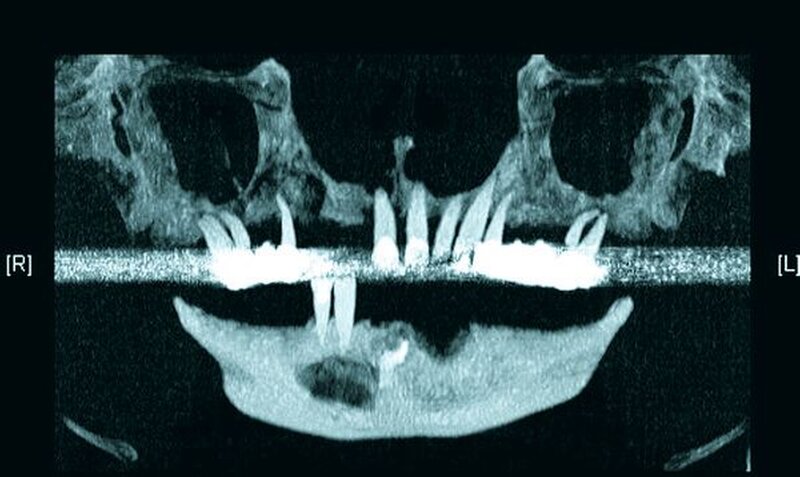

Die Computertomografie der Nasennebenhöhlen (NNH-CT) (nativ) zeigte dann das Ausmaß der knöchernen Destruktion. Neben der ausgedehnten generalisierten Nekrose des Oberkiefers konnte nebenbefundlich eine zystische Läsion im Bereich des Unterkiefers Regio 41 bis 45 diagnostiziert werden. Voraussichtlich ging diese vom Wurzelrest des Zahnes 41 aus. Weiterhin bestand eine totale Verschattung beider Sinus maxillaris und eine akzentuierte Lymphadenopathie in allen abgebildeten Leveln.